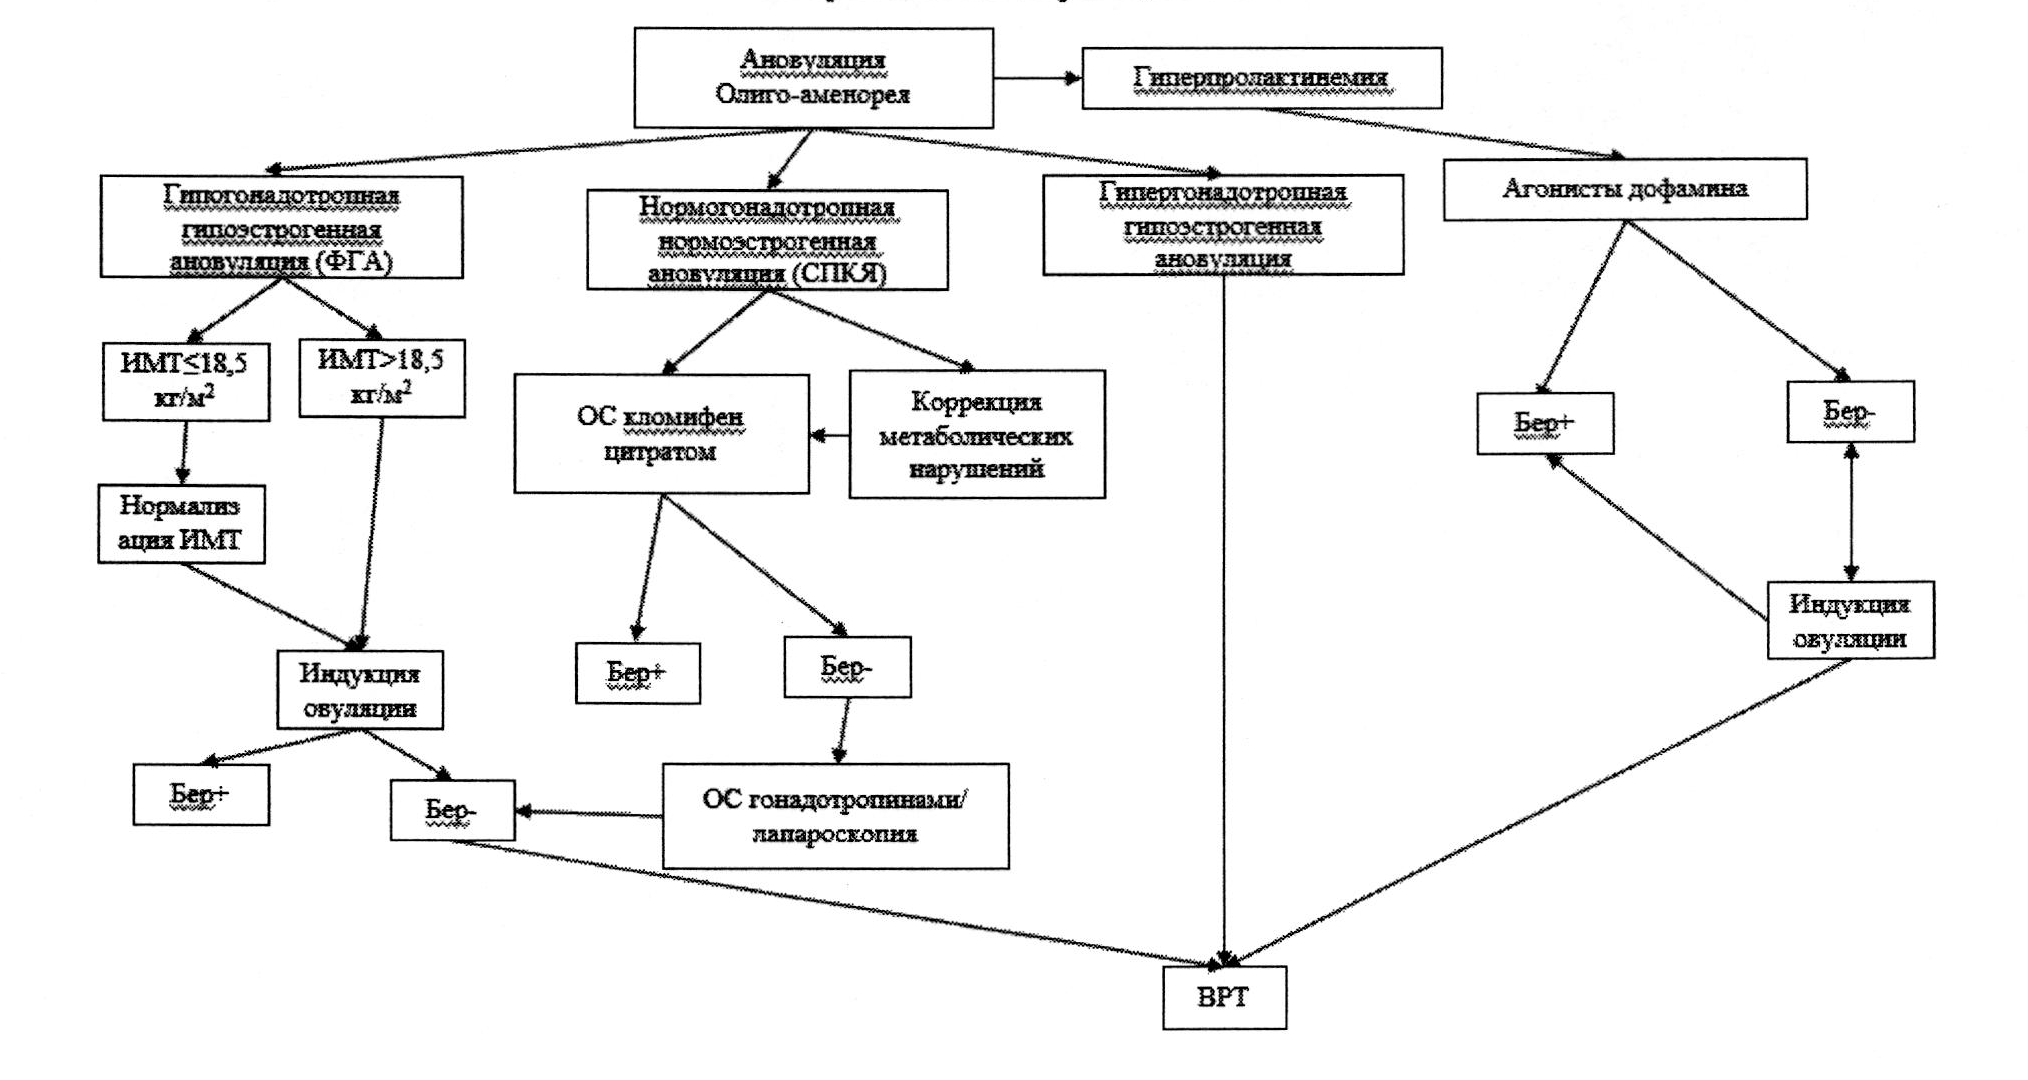

4. Женское бесплодие, связанное с отсутствием овуляции (MKБ-10/N97.0)

4.1. Определение, классификация, диагностика и лечение

Определение

Эндокринное бесплодие - отсутствие беременности в течение 12 месяцев, связанное с нарушением овуляции: ановуляцией (отсутствием овуляции) или олигоовуляцией (редкими овуляциями).

Классификация

ВОЗ классифицирует нарушения овуляции на 4 группы [43]:

Группа I: гипогонадотропная гипоэстрогенная ановуляция (функциональная гипоталамическая аменорея, гипогонадотропный гипогонадизм);

Группа II: нормогонадотропная нормоэстрогенная ановуляция (синдром поликистозных яичников - СПКЯ);

Группа III группа: гипергонадотропная гипоэстрогенная ановуляция (преждевременная недостаточность яичников, дисгенезия гонад);

Группа IV: гиперпролактинемия.

4.2. Группа I. Гипогонадотропная гипоэстрогенная ановуляция

Определение. Данная группа нарушений включает функциональную гипоталамическую аменорею (ФГА), реже гипогонадотропный гипогонадизм (в т.ч. синдром Кальмана), гипопитуитаризм. Для этих состояний, характерна первичная или вторичная аменорея, характеризующаяся низким уровнем гонадотропинов и эстрогенов в сыворотке крови.

Рекомендации по лечению бесплодия [45]

- Индукцию овуляции у женщин с ФГА рекомендовано проводить только после достижения ИМТ>18,5  ввиду повышенного риска акушерских осложнений (потеря плода, рождение детей с малым весом для гестационного возраста, преждевременные роды и кесарево сечение).

- У пациенток с ФГА при достаточном уровне эстрадиола для овариальной стимуляции можно использовать кломифен.

- Для овариальной стимуляции следует использовать препараты группы менотропинов, содержащих комбинацию ФСГ и ЛГ.

- В случае неэффективности овариальной стимуляции с использованием непрямых/прямых индукторов овуляции рекомендовано проведение программ ВРТ.

4.3. Группа II. Нормогонадотропная нормоэстрогенная ановуляция (синдром поликистозных яичников) (МКБ-10/Е28.2)

Рекомендации по лечению бесплодия при СПКЯ:

- изменение образа жизни с целью нормализации массы тела;

- использование кломифена в качестве первой линии терапии;

- при неэффективности кломифена в качестве второй линии терапии проводится овариальная стимуляция гонадотропинами или лапароскопия;

- при неэффективности овариальной стимуляции и лапароскопии показано проведение программ ВРТ.

4.4. Группа III. Гипергонадотропная гипоэстрогенная ановуляция (МКБ-10/Е28.3)

Рекомендации по лечению бесплодия у пациенток с ПНЯ [47]:

- рекомендуется проведение программ ВРТ;

4.5. Группа IV. Гиперпролактинемия (МКБ-10/Е22.1)

Рекомендации по лечению бесплодия у пациенток с гиперпролактинемией [48], [49]

- В качестве первого этапа помощи при лекарственно-индуцированной гиперпролактинемии рекомендовано отменить лекарственное средство, если это клинически возможно. В противном случае следует заменить препарат на аналогичный, но не вызывающий гиперпролактинемию. При невозможности перевода на другое лекарственное средство необходимо рассмотреть целесообразность назначения агонистов дофамина после консультации с лечащим врачом.

- Рекомендовано проводить терапию агонистами дофамина для снижения уровня пролактина, уменьшения размеров опухоли, восстановления функции гонад у пациенток с симптоматическими пролактин-секретирующими аденомами.

- При выборе препарата агонистов дофамина необходимо отдавать предпочтение каберголину, потому что он более эффективен в отношении нормализации уровня пролактина и уменьшения размеров опухоли гипофиза.

- Наиболее благоприятным фоном для зачатия является полная нормализация уровня пролактина и уменьшение размеров опухоли менее 10 мм.

- Пациенткам с микро- или макроаденомами, резистентными к лечению агонистами дофамина, или в случаях непереносимости медикаментозной терапии, целесообразно рассмотреть вопрос о проведении хирургического лечения.

- При подтверждении факта наступления беременности терапию агонистами дофамина следует отменить.